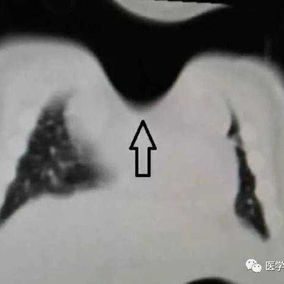

The patient was a one-month-old infant who was discovered to have an abnormality in the anterior chest wall shortly after birth. Specifically, there was a pronounced depression in the midline of the upper chest wall where the protection of bone structures was noticeably absent. The infant was diagnosed with sternal cleft and congenital heart disease. Due to the infant's poor health, surgical intervention has been postponed temporarily. Over time, the infant's condition gradually worsened, resulting in breathing difficulties and triggering a lung infection.

Preoperative Examination

There is a noticeable depression in the center of the chest wall, accompanied by obvious paradoxical respiration. This area shows large-scale deficiency or absence of bone structures, with only about 1 cm of bone structure remaining at the inferior end of the sternum, connecting both sides of the chest wall. Additionally, the patient suffers from congenital heart diseases, including ventricular septal defect and patent foramen ovale, which have led to abnormal heart rhythms and sinus tachycardia.